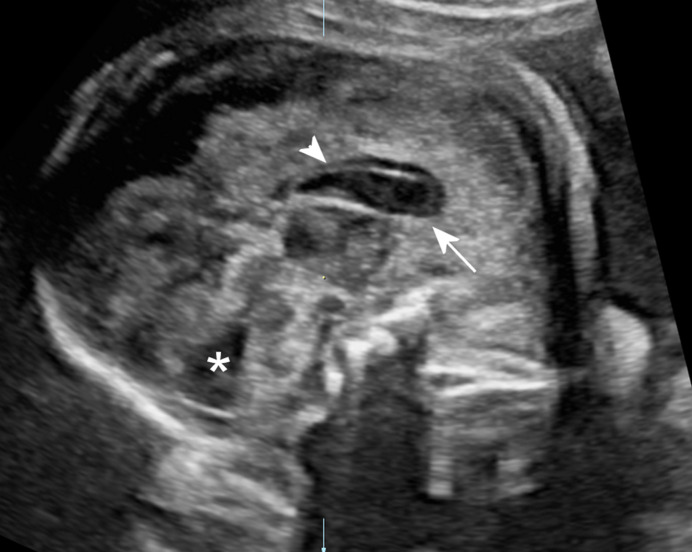

Results: Seventy-two patients were included in our cohort. In 76% infection occurred in the 1st T or periconceptional. In 12 patients, the exact time of infection was inconclusive, including two cases of secondary infection. In 34.7%, a callosal anomaly was observed and it was never isolated. CNS abnormalities included: periventricular hyperechogenicity (PVHE) 55.5%, calcifications 52%, ventriculomegaly 33%, periventricular pseudocysts 31.4%, occipital cysts 22.2%, echogenic ganglionic eminence 30.5%, lentostriatal vasculopathy 26.4%, sulcation abnormalities 22.2%, cerebellar findings 18% and HC below -2 SD 18%. In 19 cases, the CC was short with calcifications in four. In one case, the insult was severe and in another the CC was absent. The most common association with CC insult was PVHE (56%) and calcifications (52%).

Abstract Image